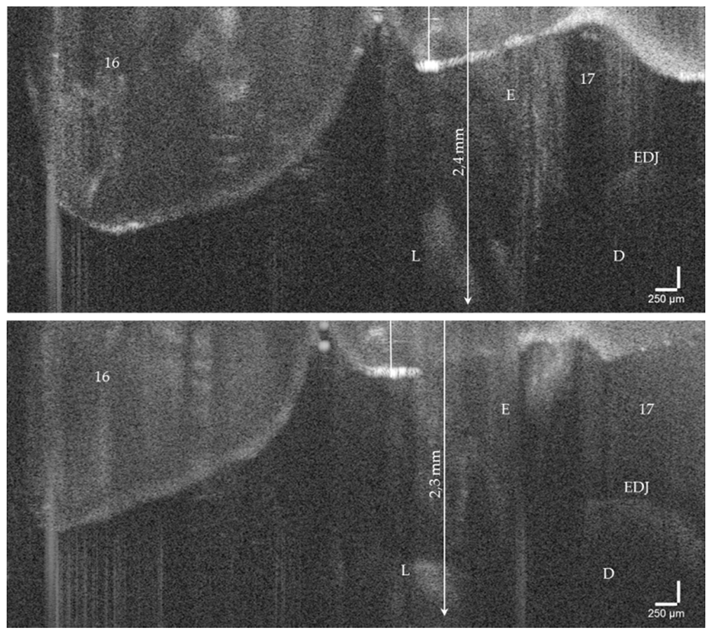

On hard tooth tissues, the imaging depth was up to 2.5 mm (Figure 6). The spatial resolution of the probe also partially allowed the visualization of superficial tissue structures of the gingiva (Figure 4e,f). The 90°-optics and the ergonometric design of the probe allowed the dentist to manually image all occlusal, vestibular, oral, and proximal tooth surfaces including those of the second molars and the occlusal, oral and proximal surfaces of the third molars. The vestibular surfaces of third molars and proximal surface areas of the molars within a “blind spot” at a distance greater than 2.5 mm from the tooth surfaces could not be imaged. While a B-scan is recorded in real time, the scan time for a C-scan is approximately 28 seconds.

Figure 6.

OCT cross-sectional image of an early approximal enamel carious lesion (L; ICDAS, Code 2) on tooth 17 in vivo. The lesion can be localized to a depth of 2.4 mm below the enamel surface. As a result of focusing on deeper structures, the tooth surface is flipped over again. Enamel (E), dentin (D), enamel-dentin junction (EDJ). The vertical scales are related to refractive index n = 1.0 (see the remark in Figure 4).